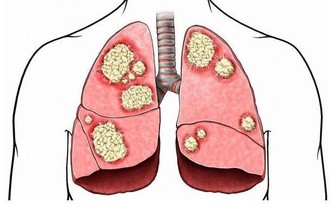

腎結石是一種常見的泌尿係統疾病,指發生於腎盂、腎盞及腎孟與輸尿管連接部的結石,多見於 30-60 歲人群,且男性發病率高於女性,近年來發病率有上升的趨勢。為什麼會患腎結石呢?研究顯示,除了泌尿係統感染、梗阻、自身代謝性疾病及遺傳因素外,腎結石的發病與不合理飲食關係密切。